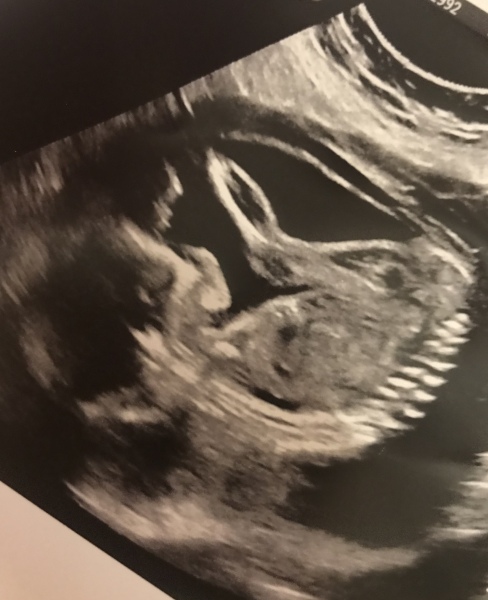

Garry1992 · 13/01/2024 14:59

When I went for my 12 week scan they were unable to takr the NT measurement due to baby being in a difficult position. I was told I'd have to come back and they will re scan me, the woman who performed the scan took me to reception where she told them to book me in for a scan in two weeks time, appointment made and off I went.

My partner and I wanted to know the gender of baby before Christmas so we booked a private scan, they checked baby over and told we were having a healthy and active baby boy.

yesterday I finally had my mid term scan (22weeks to the day) once again baby is in a difficult position curled up and not wanting to be scanned, she didn't manage to get all the measurements but she did get the NT which came back as 6.8

She did this measurement a few times and said she wasn't happy so has referred me onto to the Fetal Medicine Specialist this coming Wednesday for them to scan and finish off the mid term scan. I wasn't old anything other then it's coming back higher then she would like and wants it to be checked, she said most cases she does this resolves itself and is no issue, she said don't be concerned or worried.